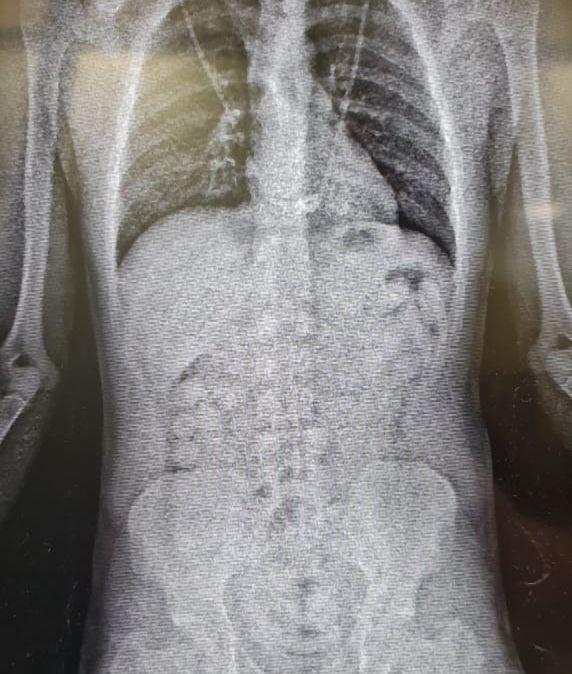

| Cápsulas de cocaína vistas em raio-x feita pela Polícia Federal / Foto: Divulgação/Polícia Federal |